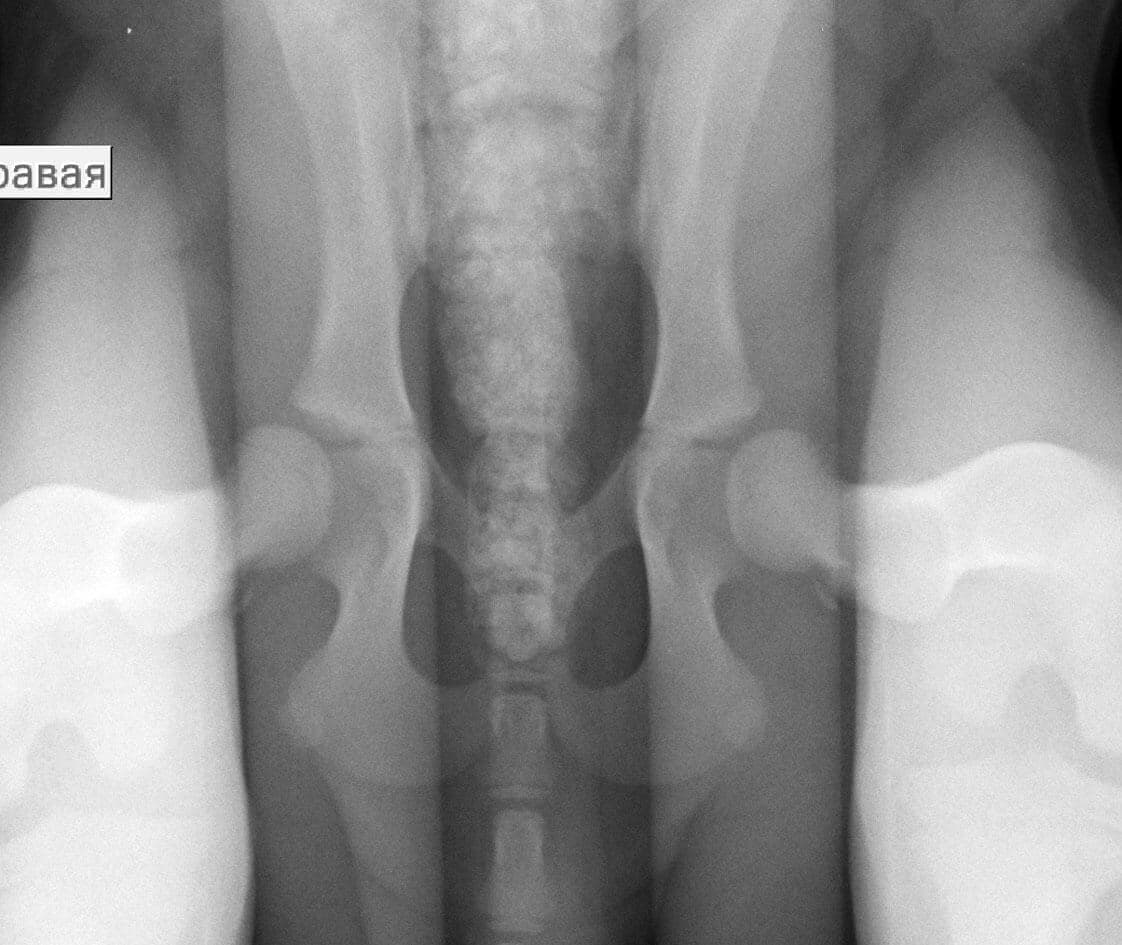

ПРИМЕР ОБСЛЕДОВАНИЯ НА ВЕРОЯТНОСТЬ РАЗВИТИЯ ОСТЕОАРТРОЗА В 4 МЕСЯЦА.

Щенок лабрадора 4 мес. Уже на проекции “лежа на спине с вытянутыми ногами” видно недостаточное покрытие головок бедренной кости крышей вертлужной впадины.

На снимке “дистракционная проекция” виден значительный выход головки бедренной кости из вертлужной впадины, что говорит о значительной вероятности развития остеоартроза в ближайшие годы жизни животного.